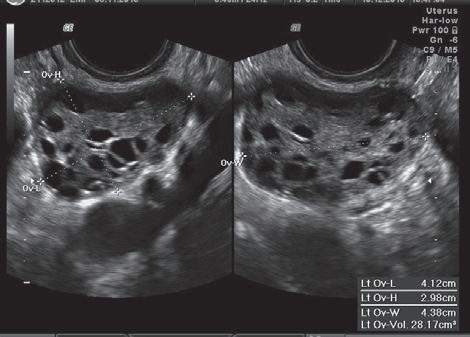

figura 7.3.1 – Imagens de ecografia pélvica usando sonda vaginal: a – corte transversal de útero normal (endométrio trilaminar, de impregnação estrogénica); B – quisto de endometriose do ovário; C – ovários poliquísticos.

Uma situação em que os critérios estão claramente definidos diz respeito aos ovários poliquísticos. Usando sondas vaginais de última geração (8 MHz), os critérios são: 20 folículos medindo 2 -9 mm em cada ovário e/ou um volume ≥10 cc em cada ovário, na ausência de folículo dominante, corpo amarelo ou quisto(s).

Se se tiver acesso apenas a condições técnicas mais antigas ou a sonda abdominal, o critério será um volume ≥10 cc em cada ovário, uma vez que a avaliação do número de folículos muito pequenos é pouco fiável (Teede HJ et al., 2023).